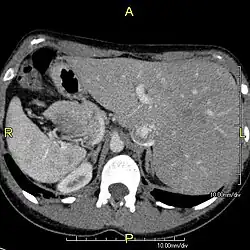

The condition affects all major structures within the thorax and abdomen. Generally, the organs are simply transposed through the sagittal plane. The heart is located on the right side of the thorax, the stomach and spleen on the right side of the abdomen and the liver and gall bladder on the left side. The heart's normal right atrium occurs on the left, and the left atrium is on the right. The lung anatomy is reversed and the left lung has three lobes while the right lung has two lobes. The intestines and other internal structures are also reversed from the normal, and the blood vessels, nerves, and lymphatics are also transposed.

If the heart is swapped to the right side of the thorax, it is known as "situs inversus with dextrocardia" or "situs inversus totalis". If the heart remains on the normal left side of the thorax, a much rarer condition (1 in 2,000,000 of the general population), it is known as "situs inversus with levocardia" or "situs inversus incompletus".

Diagnosis of situs inversus can be made using imaging techniques such as x-ray, ultrasound, CT scan, and magnetic resonance imaging (MRI).[9]